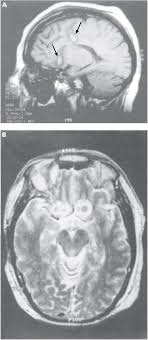

Asymmetries In The Anterior Cingulate Cortex Example Of Mri Sagittal Download Scientific Diagram

Asymmetries In The Anterior Cingulate Cortex Example Of Mri Sagittal Download Scientific Diagram from www.researchgate.net